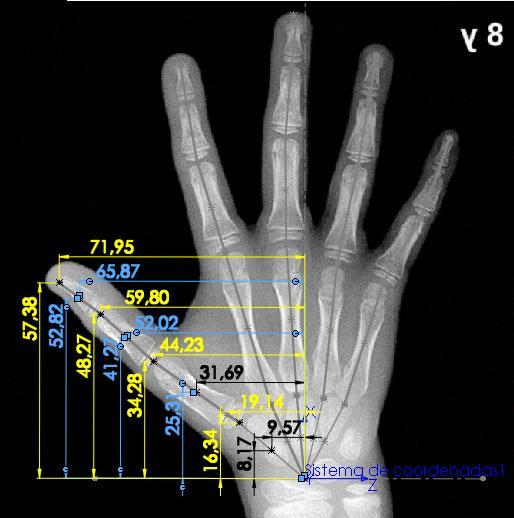

Teniéndose el carpograma de referencia, se importa dicha imagen a SolidWorks, con el fin de realizar el análisis de dimensiones correspondiente. Primero se determinan los puntos de análisis para cada hueso de la mano, acorde a las recomendaciones dadas en “Hand Bone Age A Digital Atlas of Skeletal Maturity”, obteniéndose una imagen con puntos de referencia (Figura 12).

Posteriormente, se extienden líneas entre los puntos de análisis para cada una de las cadenas cinemáticas que componen la mano, esto con el fin de aproximar la imagen del carpograma de referencia a la representación esquemática planteada anteriormente (Figura 10), y así poder dimensionar la representación esquemática. Una vez hecho esto, se obtiene la imagen que se observa en la Figura 13.

Figura 13. Carpograma de referencia con adición de líneas representando cada cadena cinemática

Fuente: (Gilsanz & Ratib, 2005); Edición: SolidWorks

Una vez se tiene la representación esquemática de la mano humana planteada sobre el carpograma de referencia en un software CAD, es posible realizar mediciones, las cuales permiten conocer las dimensiones en milímetros de cada uno de los eslabones de las cadenas cinemáticas (Figura 14), así como también los ángulos de orientación de cada uno de ellos (Figura 15), los cuales posteriormente se analizarán en la determinación del modelo.

Los resultados de las mediciones realizadas sobre el carpograma de referencia se presentan en las Tablas 3, 4 y 5. Se emplea para esto la nomenclatura citada en la Tabla 2.

Tabla 3. Medidas de magnitud realizadas sobre el carpograma de referencia.

Pulgar [mm] Indice [mm] Medio [mm] Anular [mm] Meñique [mm]

Lt,D 15,19 Li,D 11,33 Lm,D 12,65 La,D 13,03 Le,D 10,96 Lt,P 20,93 Li,Mi 17,67 Lm,Mi 21,22 La,Mi 19,83 Le,Mi 13,84 Lt,M 30,74 Li,P 27,51 Lm,P 30,81 La,P 28,99 Le,P 21,58 Li,Me 46,53 Lm,Me 45,06 La,Me 40,21 Le,Me 37,66

De igual manera se mide la orientación de cada cadena cinemática respecto al eje X.

Tabla 4. Orientación de cada cadena cinemática sobre el carpograma de referencia

Ángulo [rad]

Pulgar -0,95

Indice -0,29

Medio -0,07

Anular 0,1 Meñique 0,31

Adicional a esto, se realiza la medición de las coordenadas (x,y,z) de cada uno de los vectores de orientación (u), que modelan la zona de los huesos carpos y que son el punto de partida para cada cadena cinemática (t, i, m, a, e), según la nomenclatura usada en la representación esquemática de la Figura 10.

Tabla 5. Coordenadas de los vectores de orientación.

utx 16,34 uix 21,91 umx 24,38 uax 23,55 uex 21,91 uty 0 uiy 0 umy 0 uay 0 uey 0 utz -19,14 uiz -9,9 umz -2,32 uaz 5,45 uez 11,69

Tomadas estas medidas se tiene completamente caracterizada la representación esquemática planteada con base en el carpograma de referencia de un niño de 8 años de edad, permitiéndose así la determinación de un modelo cinemático.